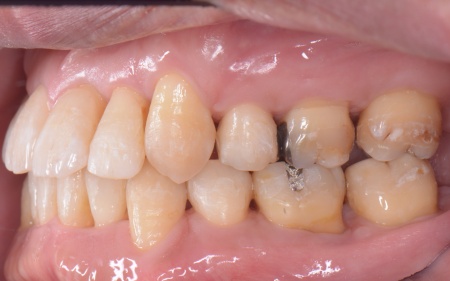

| カウンセリング | 拝見したところ、上下の歯は、ずれたりねじれたりしてデコボコに生えており、著しく歯並びが乱れていました。

またレントゲン撮影をして確認すると、右上前歯は顎の骨の中に埋まっている骨性埋伏(こっせいまいふく)の状態でした。 さらに、左下奥歯は重度の歯周病であり、歯を支えている骨が一部溶けていることが判明しました。 以上のことから、歯並びを整える矯正治療と歯周病の治療を併せて行う必要があると診断しました。 |